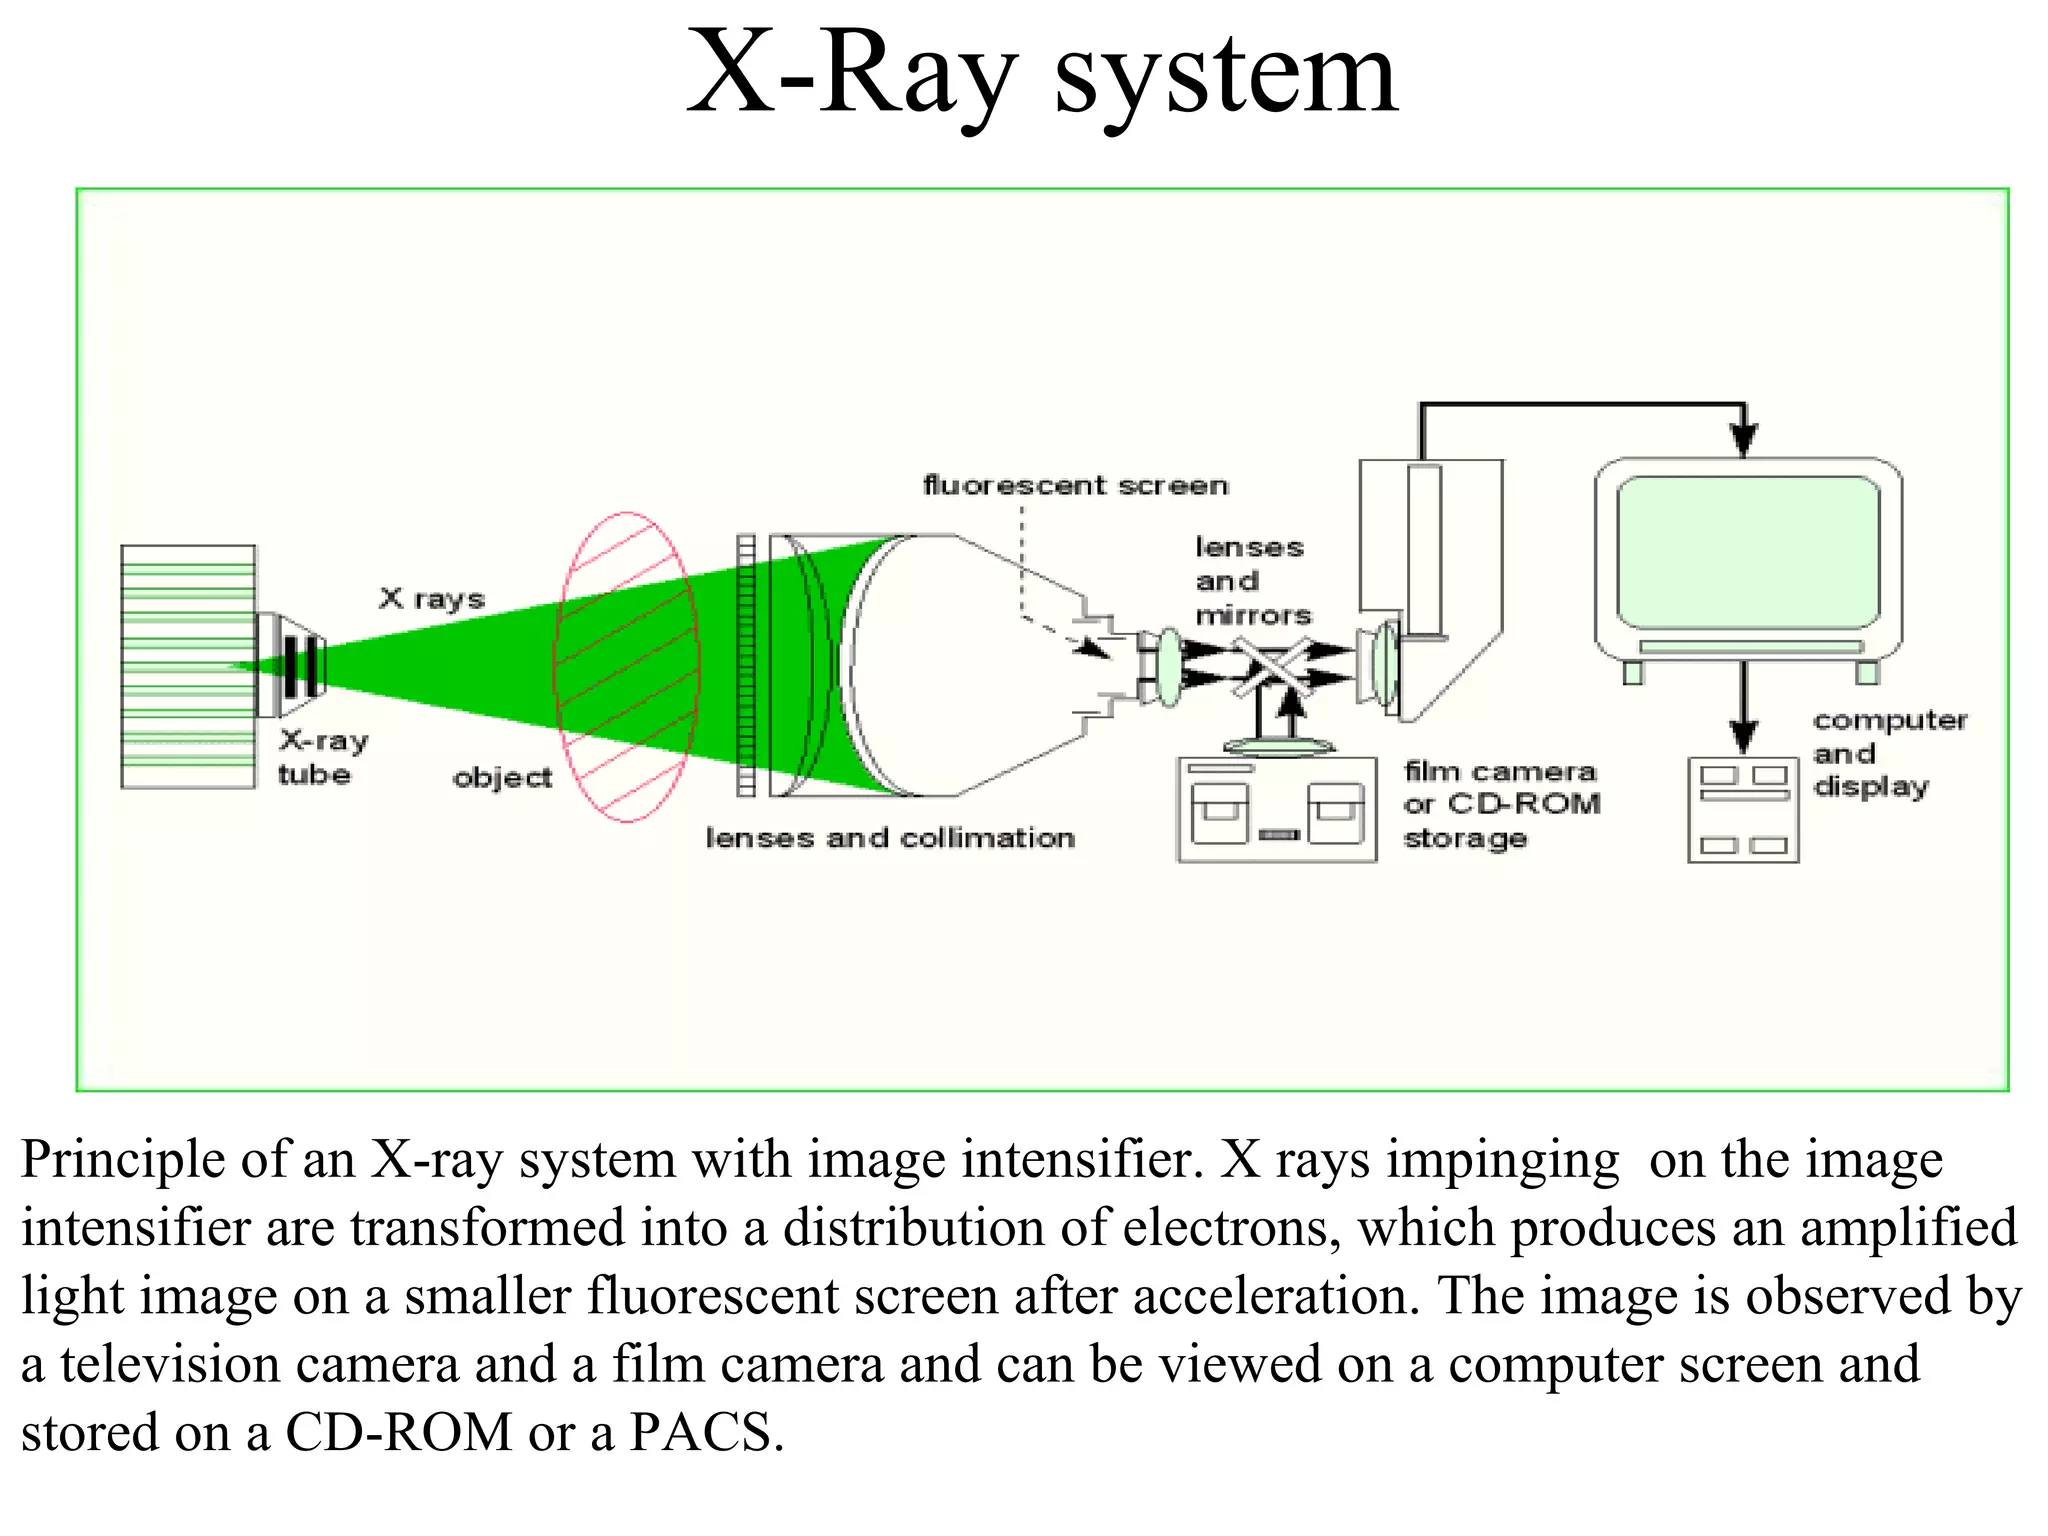

The document discusses various medical imaging modalities including x-rays, computed tomography (CT), and digital mammography. It describes the basic principles and historical development of these technologies, how images are formed, and what types of anatomical features and abnormalities they can detect. Key advances include the development of digital systems that allow image manipulation and remote consultation. While promising, digital mammography still faces challenges around resolution and cost.